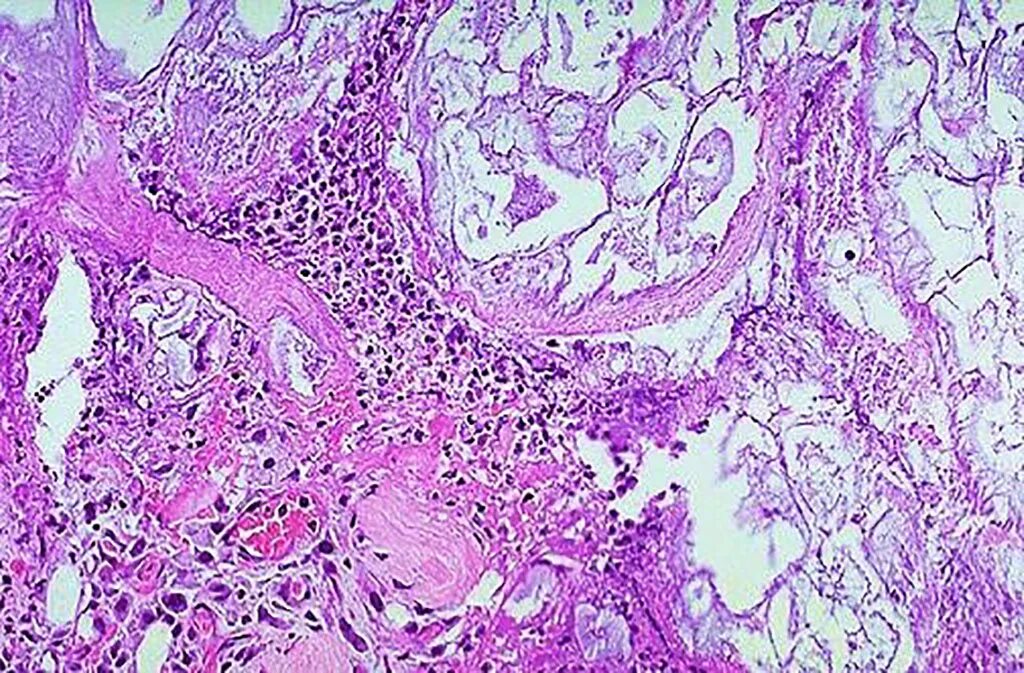

Гистология фиброзные фрагменты